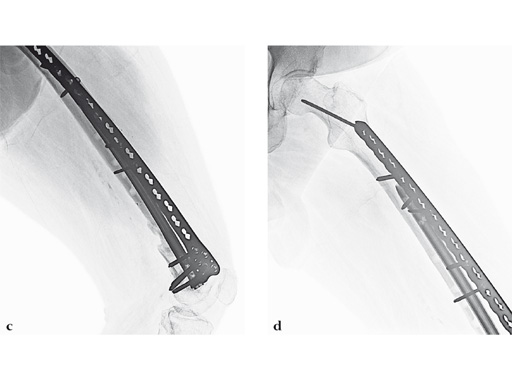

Case 3: A 53-year-old man with hypotestosteronism, low vitamin D levels, and calcium metabolism problems. Recalcitrant atrophic nonunion of his distal femur after three surgical attempts with an extension and flexion contracture of his knee.

The VA-LCP Curved Condylar Plate was used to avoid previous enlarged screw holes and allow for stable fixation in the patient's osteoporotic distal segment. Secondary to his metabolic and mechanical problems, the decision was made to proceed with an endosteal implant and place interlocking screws through that implant from the VA-LCP Curved Condylar Plate. The combination of the retrograde/antegrade femoral nail and VA-LCP provides a very stable mechanical environment for the expected prolonged healing response.